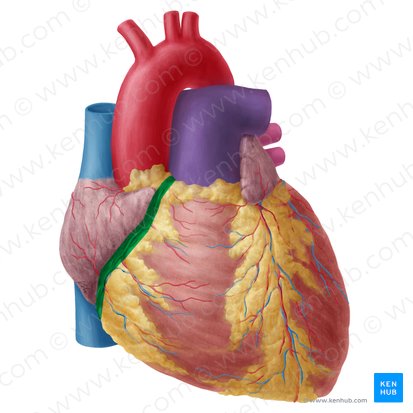

coronary (atrioventricular) sulcus

anterior interventricular sulcus

posterior interventricular sulcus

right coronary artery

posterior interventricular artery

left coronary artery

anterior interventricular artery

circumflex artery

coronary sinus